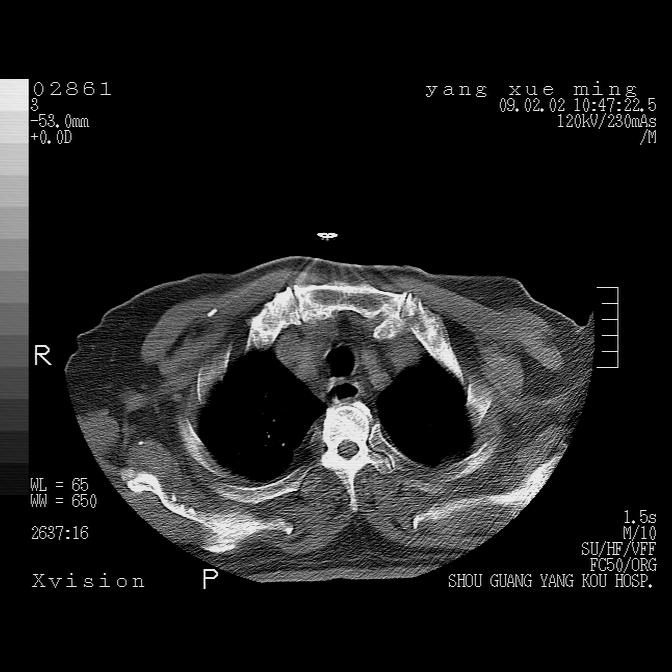

以下是引用zbp537在2009-2-3 19:08:00的发言:[br]我诊断为肺泡性肺水肿。[br]诊断依据:[br]1、心影普遍增大,肺血管增粗,并见絮状高密度影,肺门改变显著。[br]2、临床上表现胸闷咳嗽,无发烧,不是一个典型的肺部感染的病史。

以下是引用lkc8963在2009-2-3 20:11:00的发言:[br]1)右上肺陈旧病灶。2)右下肺团块及团片影,影像表现符合感染。3)左心增大,左冠脉钙化,符合冠心病。4)双侧肺门扩大,以左侧为著,肺动脉干略粗,左上肺局限性气肿,为谨慎起见,需除肿瘤,建议增强。

以下是引用lkc8963在2009-2-3 20:11:00的发言:[br]1)右上肺陈旧病灶.2)右下肺团块及团片影,影像表现符合感染.3)左心增大,左冠脉钙化,符合冠心病.4)双侧肺门扩大以左侧为著,肺动脉干略粗,左上肺局限性气肿,为谨慎起见,需除肿瘤,建议增强.